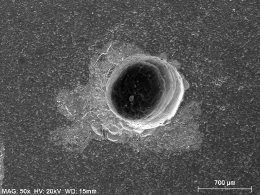

Preparo com CVDentus: Sem danos à membrana pulpo-dentinária. Preservação dos odontoblastos (CO), dentida tubular (DT), pré-dentina (PD) e zona acelular (ZA).